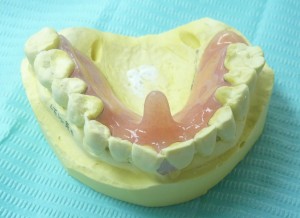

私の先代メインTPC (即時重合レジンで直接法で作成)

↑ わかりやすくするために色を塗っています ↑